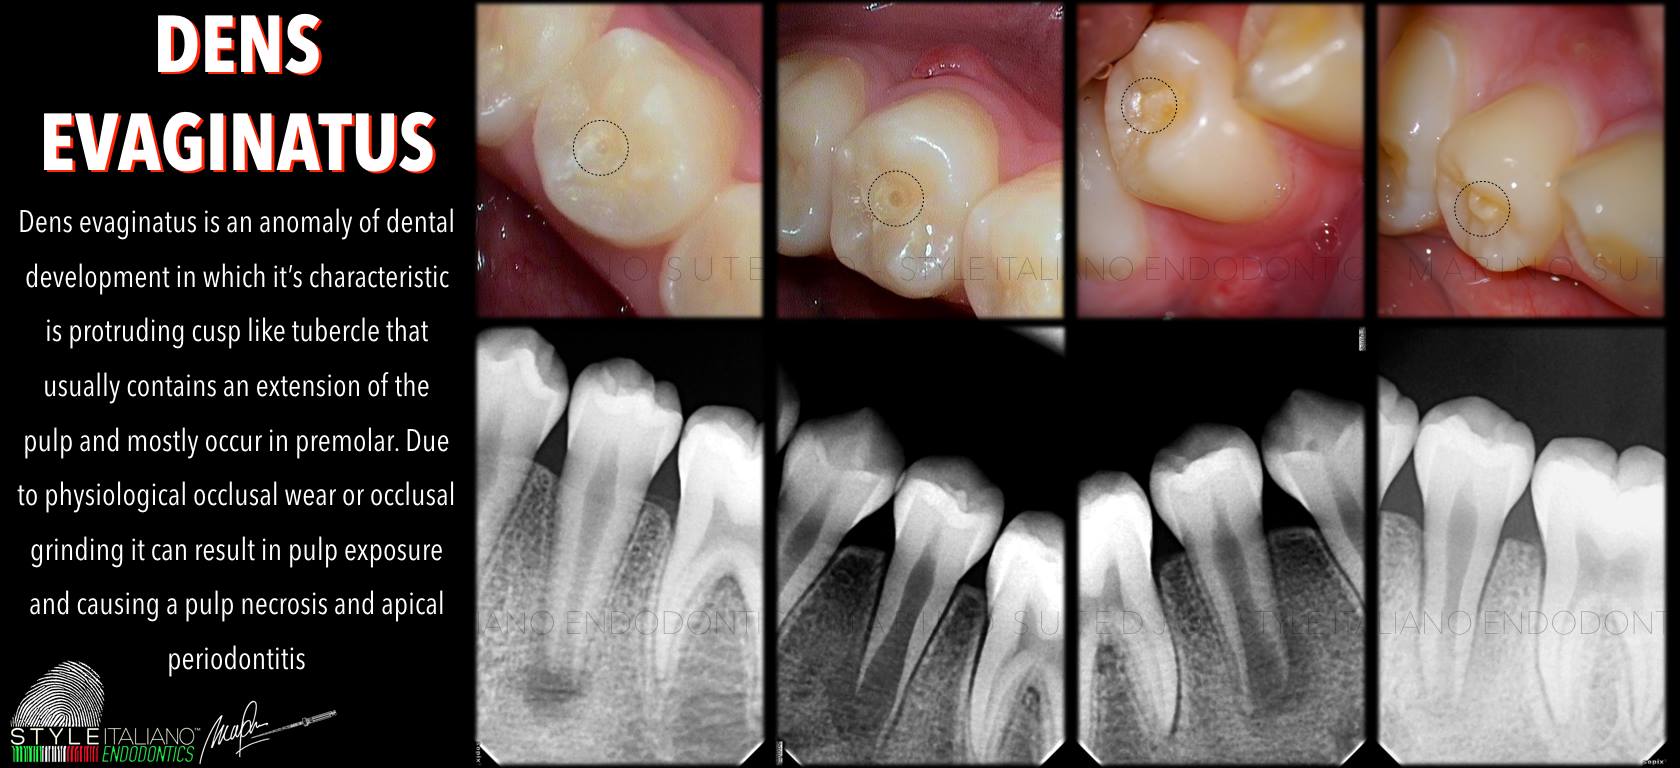

Núm phụ mặt nhai là một bất thường phát triển răng, thuộc nhóm Dens evaginatus, biểu hiện bằng một múi dư nhô lên ở mặt nhai, thường gặp nhất ở răng tiền cối hàm dưới (Leong’s premolar). Về mặt mô học, núm phụ này có thể chứa: Men, Ngà Và đặc biệt: một phần mô tủy kéo dài vào trong núm. Chính yếu tố này khiến núm phụ mặt nhai trở thành nguy cơ cao gây biến chứng nội nha, đặc biệt ở bệnh nhân trẻ.

Phân loại dựa trên tình trạng tủy và mức độ phát triển chân răng:

6 nhóm lâm sàng điển hình

Đây là phân loại quan trọng giúp bác sĩ lựa chọn đúng phác đồ điều trị và tiên lượng.

Điều trị dens evaginatus cần tuân thủ các nguyên tắc cốt lõi:

Phác đồ điều trị theo từng nhóm

Nhóm I & II: Tủy bình thường

Chiến lược bảo tồn – dự phòng

- Mài chỉnh khớp cắn nhẹ nhàng

- Trám bảo vệ núm phụ bằng composite lỏng

- Theo dõi sự thoái triển của sừng tủy

Sau khi an toàn:

- Mài dần núm phụ theo từng giai đoạn

- Phục hồi bằng composite

Lưu ý:

Không mài một lần quá nhiều để tránh lộ tủy.

Nhóm III & V: Viêm tủy / hoại tử tủy – đã đóng chóp

Điều trị nội nha tiêu chuẩn

- Mở tủy – làm sạch – tạo hình

- Trám bít hệ thống ống tủy

Tiên lượng tốt nếu xử lý kịp thời.

Nhóm IV: Viêm tủy – chưa đóng chóp

Điều trị bảo tồn tủy sống

- Cắt tủy buồng bán phần (partial pulpotomy)

- Sử dụng MTA

- Phủ bên trên bằng GIC hoặc composite

Mục tiêu:

- Duy trì tủy sống- Cho phép chân răng tiếp tục phát triển

Nhóm VI: Hoại tử tủy – chưa đóng chóp

Chiến lược điều trị

- Apexification bằng MTA

- Hoặc tái sinh nội nha (Regenerative endodontics)

Trong thực hành:

- MTA apexification vẫn là lựa chọn phổ biến, hiệu quả cao